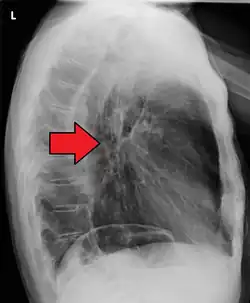

Although an occlusive tumor may be suspected on a barium swallow or barium meal, the diagnosis is best made with an examination using an endoscope. This involves the passing of a flexible tube with a light and camera down the esophagus and examining the wall, and is called an esophagogastroduodenoscopy. Biopsies taken of suspicious lesions are then examined histologically for signs of malignancy.

Additional testing is needed to assess how much the cancer has spread (see § Staging, below). Computed tomography (CT) of the chest, abdomen and pelvis can evaluate whether the cancer has spread to adjacent tissues or distant organs (especially liver and lymph nodes). The sensitivity of a CT scan is limited by its ability to detect masses (e.g. enlarged lymph nodes or involved organs) generally larger than 1 cm.[44][45] Positron emission tomography is also used to estimate the extent of the disease and is regarded as more precise than CT alone.[46] PET/MR as a novel modality has shown promising results in preoperative staging with fair feasibility and good correlation in comparison to PET/CT. It can enhance tissue differentiation with lowering the radiation dose to the patient.[47] Esophageal endoscopic ultrasound can provide staging information regarding the level of tumor invasion, and possible spread to regional lymph nodes.

-

Endoscopic image of Barrett esophagus – a frequent precursor of esophageal adenocarcinoma -

Endoscopy and radial endoscopic ultrasound images of a submucosal tumor in the central portion of the esophagus -

Contrast CT scan showing an esophageal tumor (axial view)

Contrast CT scan showing an esophageal tumor (coronal view)